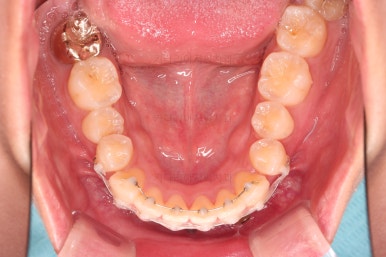

초진 시 입안의 모습입니다.

어금니 쪽은 약간 삐뚤긴 하지만 꼭 교정해야 할 정도는 아니고, 불편감 없이 비교적 잘 맞물리는 상태였습니다.

다만, 앞니ㅉㄱ이 공간이 부족해서 중간 치아들이 많이 회전되어있는데, 이를 환자분들의 표현에 따르면 "나비치아" 라고 부릅니다.

위아래 중간 앞니가 모두 나비치아처럼 되어있고요.

윗니가 아랫니보다 앞쪽으로 나와 있는 모습에 아래앞니가 윗니쪽으로 깊숙이 올라간 "과개교합" 양상을 보였습니다.

아래 앞니는 브라켓보다는 훨씬 작은 미니튜브 장치를 사용했습니다.

과개교합의 경우 브라켓을 부착하게 되면 씹히게 되어 치료과정이 수월하지 못하기 때문이죠.